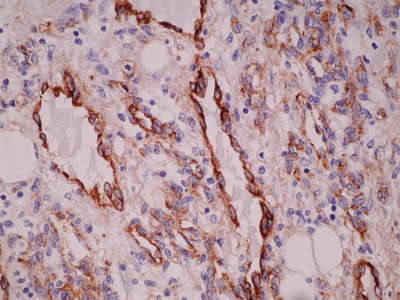

Histologically, the angiosarcomas are divided into well and poorly differentiated categories. In well-differentiated angiosarcoma, the endothelial cells form freely anastomosing, irregular vascular channels, which are lined by flat endothelial cells having enlarged hyperchromatic nuclei and occasional mitotic figures. Sometimes villous papillary formation occurs. Ill-defined borders and local infiltration are essential features. In biopsies, these characters may be absent making correct diagnosis difficult. In the poorly differentiated angiosarcoma the malignant nature is apparent with anaplastic endothelial cells forming complex vascular channels or solid sheets. The latter case often suggests a poorly differentiated carcinoma. A correct diagnosis requires immunohistochemical stain for Factor VIII or endothelial cell markers2.

Figure 1

Figure 2

Figure 3

Figure 4

Figure 5

Figure 6